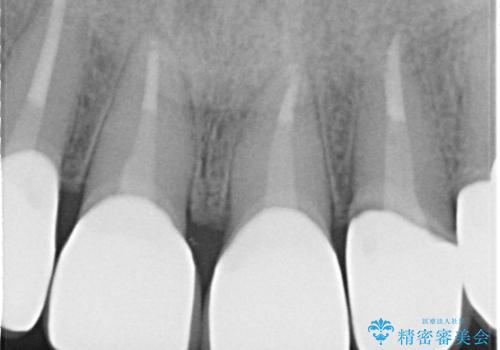

- 前歯の変色を主訴に来院されました。

歯茎のラインも整っていなかったため、手術を行いきれいな被せ物をいれることができました。

歯茎のラインを整える手術を行ったあとは、しばらく待ってから被せ物の治療を行っていきます。